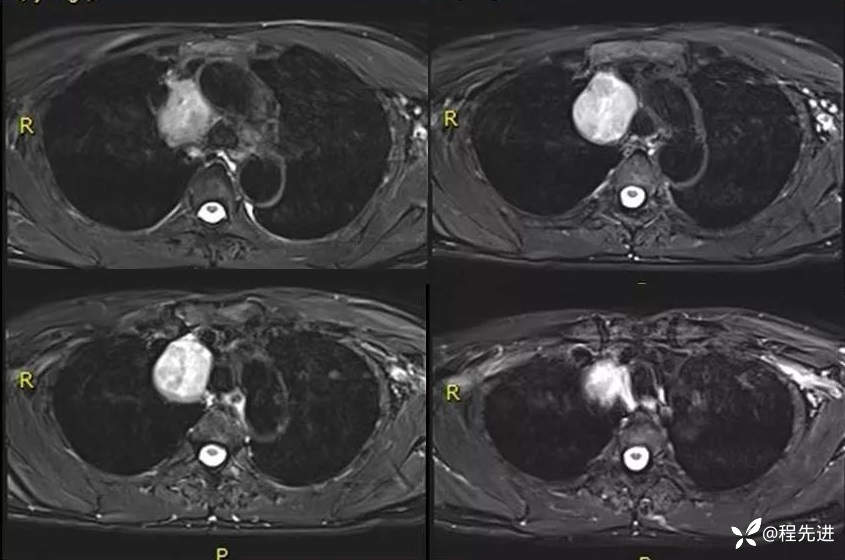

MR

T2压脂